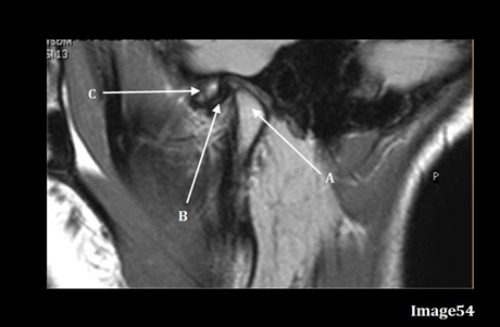

Letter A in Image 54 is pointing to:

A. Articular disk

B. Articular tubercle

C. Intervertebral disk

D. Mandibular condyle

E. Lateral epicondyle

Letter C in Image 54 is pointing to:

Image 54 is an MRI of the ______.

A. Shoulder joint

B. Hip Joint

C. TMJ

D. Pituitary gland